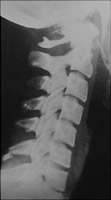

The clay-shoveler's fracture is an oblique fracture of a lower cervical spinous process, commonly C7. It results from hyperflexion, commonly from shoveling snow, although it was originally named for those who were mining clay. This is a stable injury.

- Click on the image for a larger versionALateral radiograph of the cervical spine. This is the typical clay shoveler's fracture of the lower cervical spine